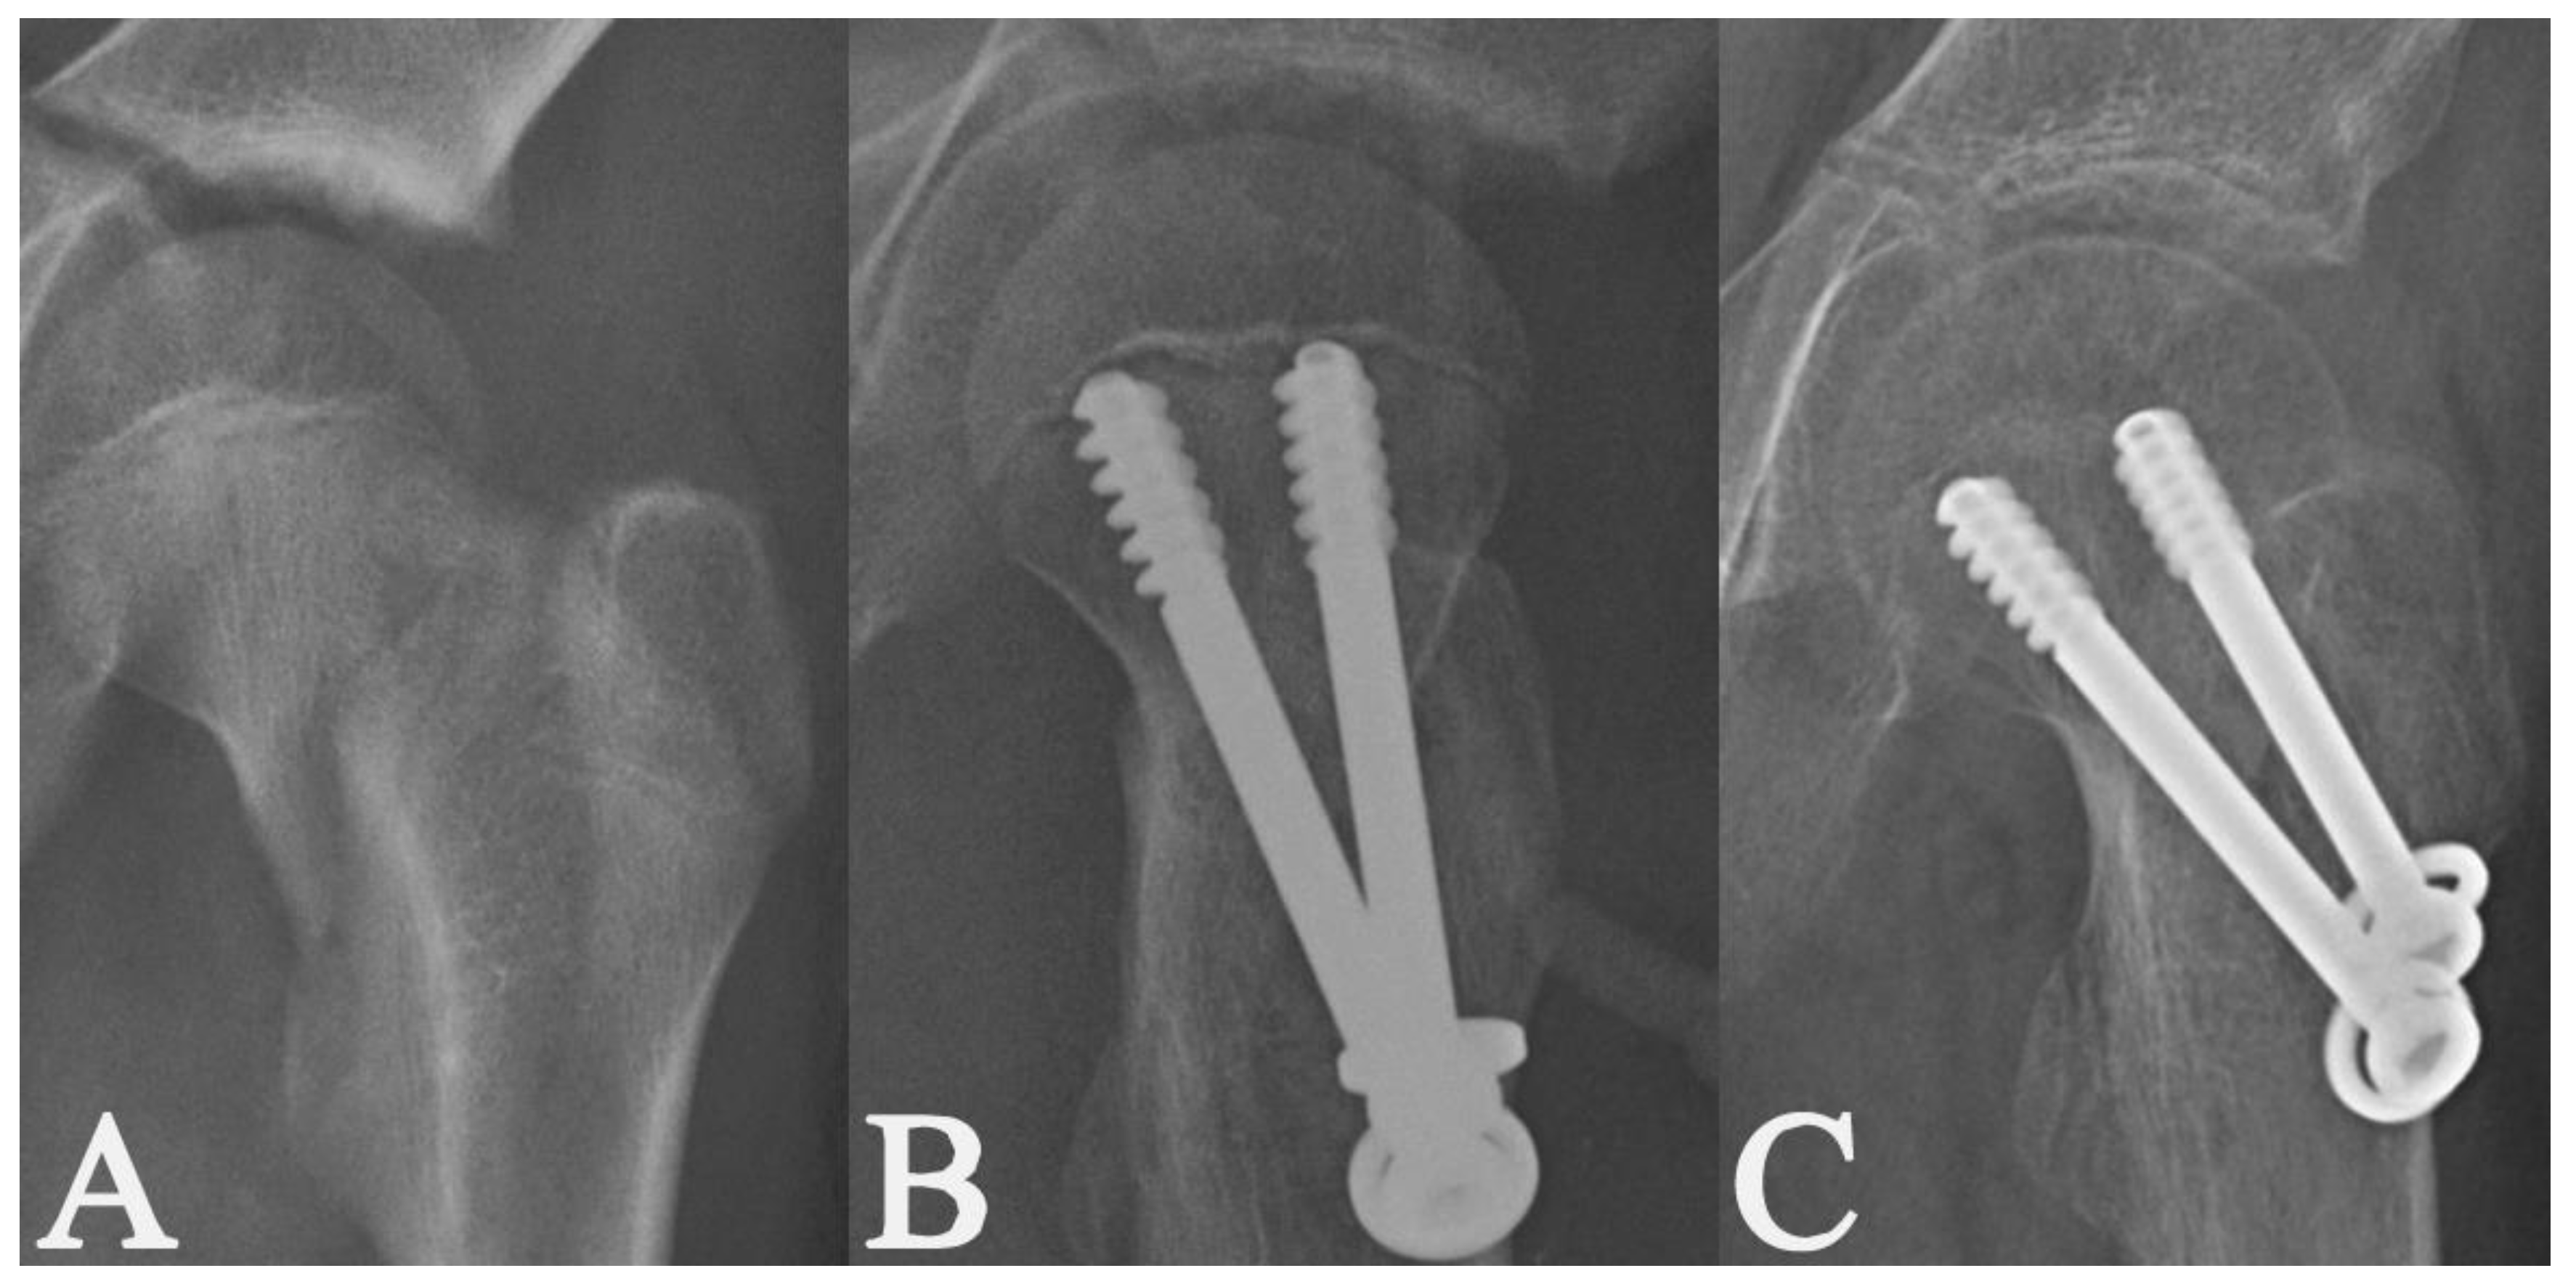

2. Materials and Methods